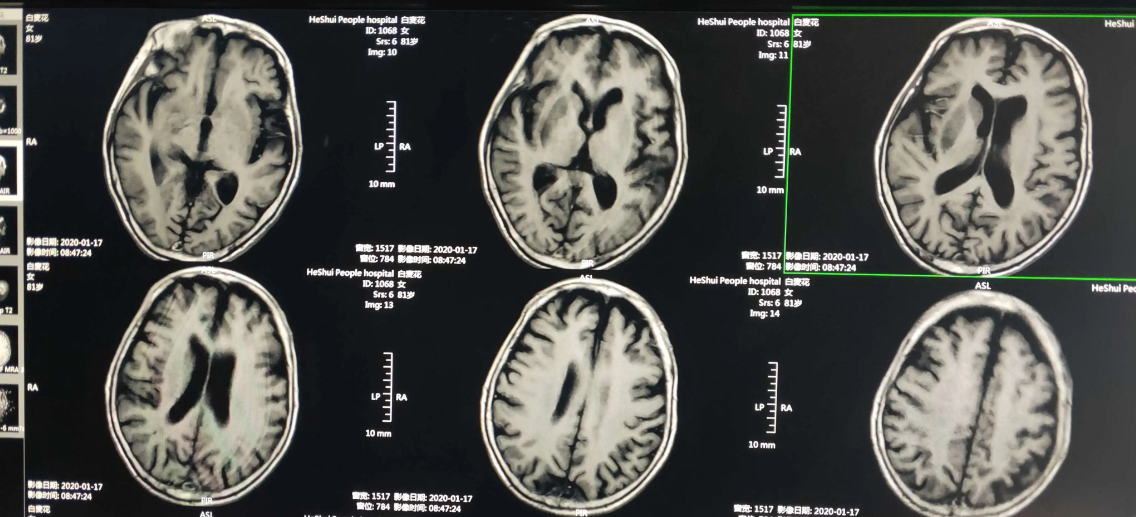

1、核磁共振图像(MRI)

核磁共振成像(Magnetic Resonance Imaging, MRI)是一种非侵入式的活体成像技术,科学将其定义为处于静磁场中的原子核在另一交变电磁场作用下发生的物理现象。通常人们所说的核磁共振就是利用核磁共振现象获取分子结构,以及人体内部结构信息的技术。共振成像的基本原理,是将人体置于特殊的磁场中,用无线电射频脉冲激发人体内氢原子核,引起氢原子核共振并吸收能量,在停止射频脉冲后,氢原子核按特定频率发出射电信号,并将吸收的能量释放出来,被体外的接受器收录,经电子计算机处理获得图像。

核磁共振成像技术提供的信息量不但大于医学影像学中的其他许多成像术,而且不同于已有的成像术。因此,它对疾病的诊断具有很大的潜在优越性。它可以直接作出横断面、矢状面、冠状面和各种斜面的体层图像,并且不会产生CT检测中的伪影;不需注射造影剂;无电离辐射,对机体不良影响较小。共振成像对检测脑内血肿、脑外血肿、脑肿瘤、颅内动脉瘤、动静脉血管畸形、脑缺血、椎管内肿瘤、脊髓空洞症和脊髓积水等疾病非常有效。同时,对腰椎椎间盘后突、原发性肝癌等疾病的诊断也很有效。

当然,共振成像也存在不足之处。它的速度相对较慢,空间分辨率不及CT,且存在运动伪影等。图像重建和超分辨率是MRI中的两项关键技术。前者通过降低空间采样率来加速MRI(但其中涉及到下采样伪影,运动伪影等等处理)相关算法比如并行成像技术,压缩感知成像等等,后者通过恢复单个退化的低分辨率(LR)图像来实现高分辨率(HR)图像,相关算法比如双三次插值等等。